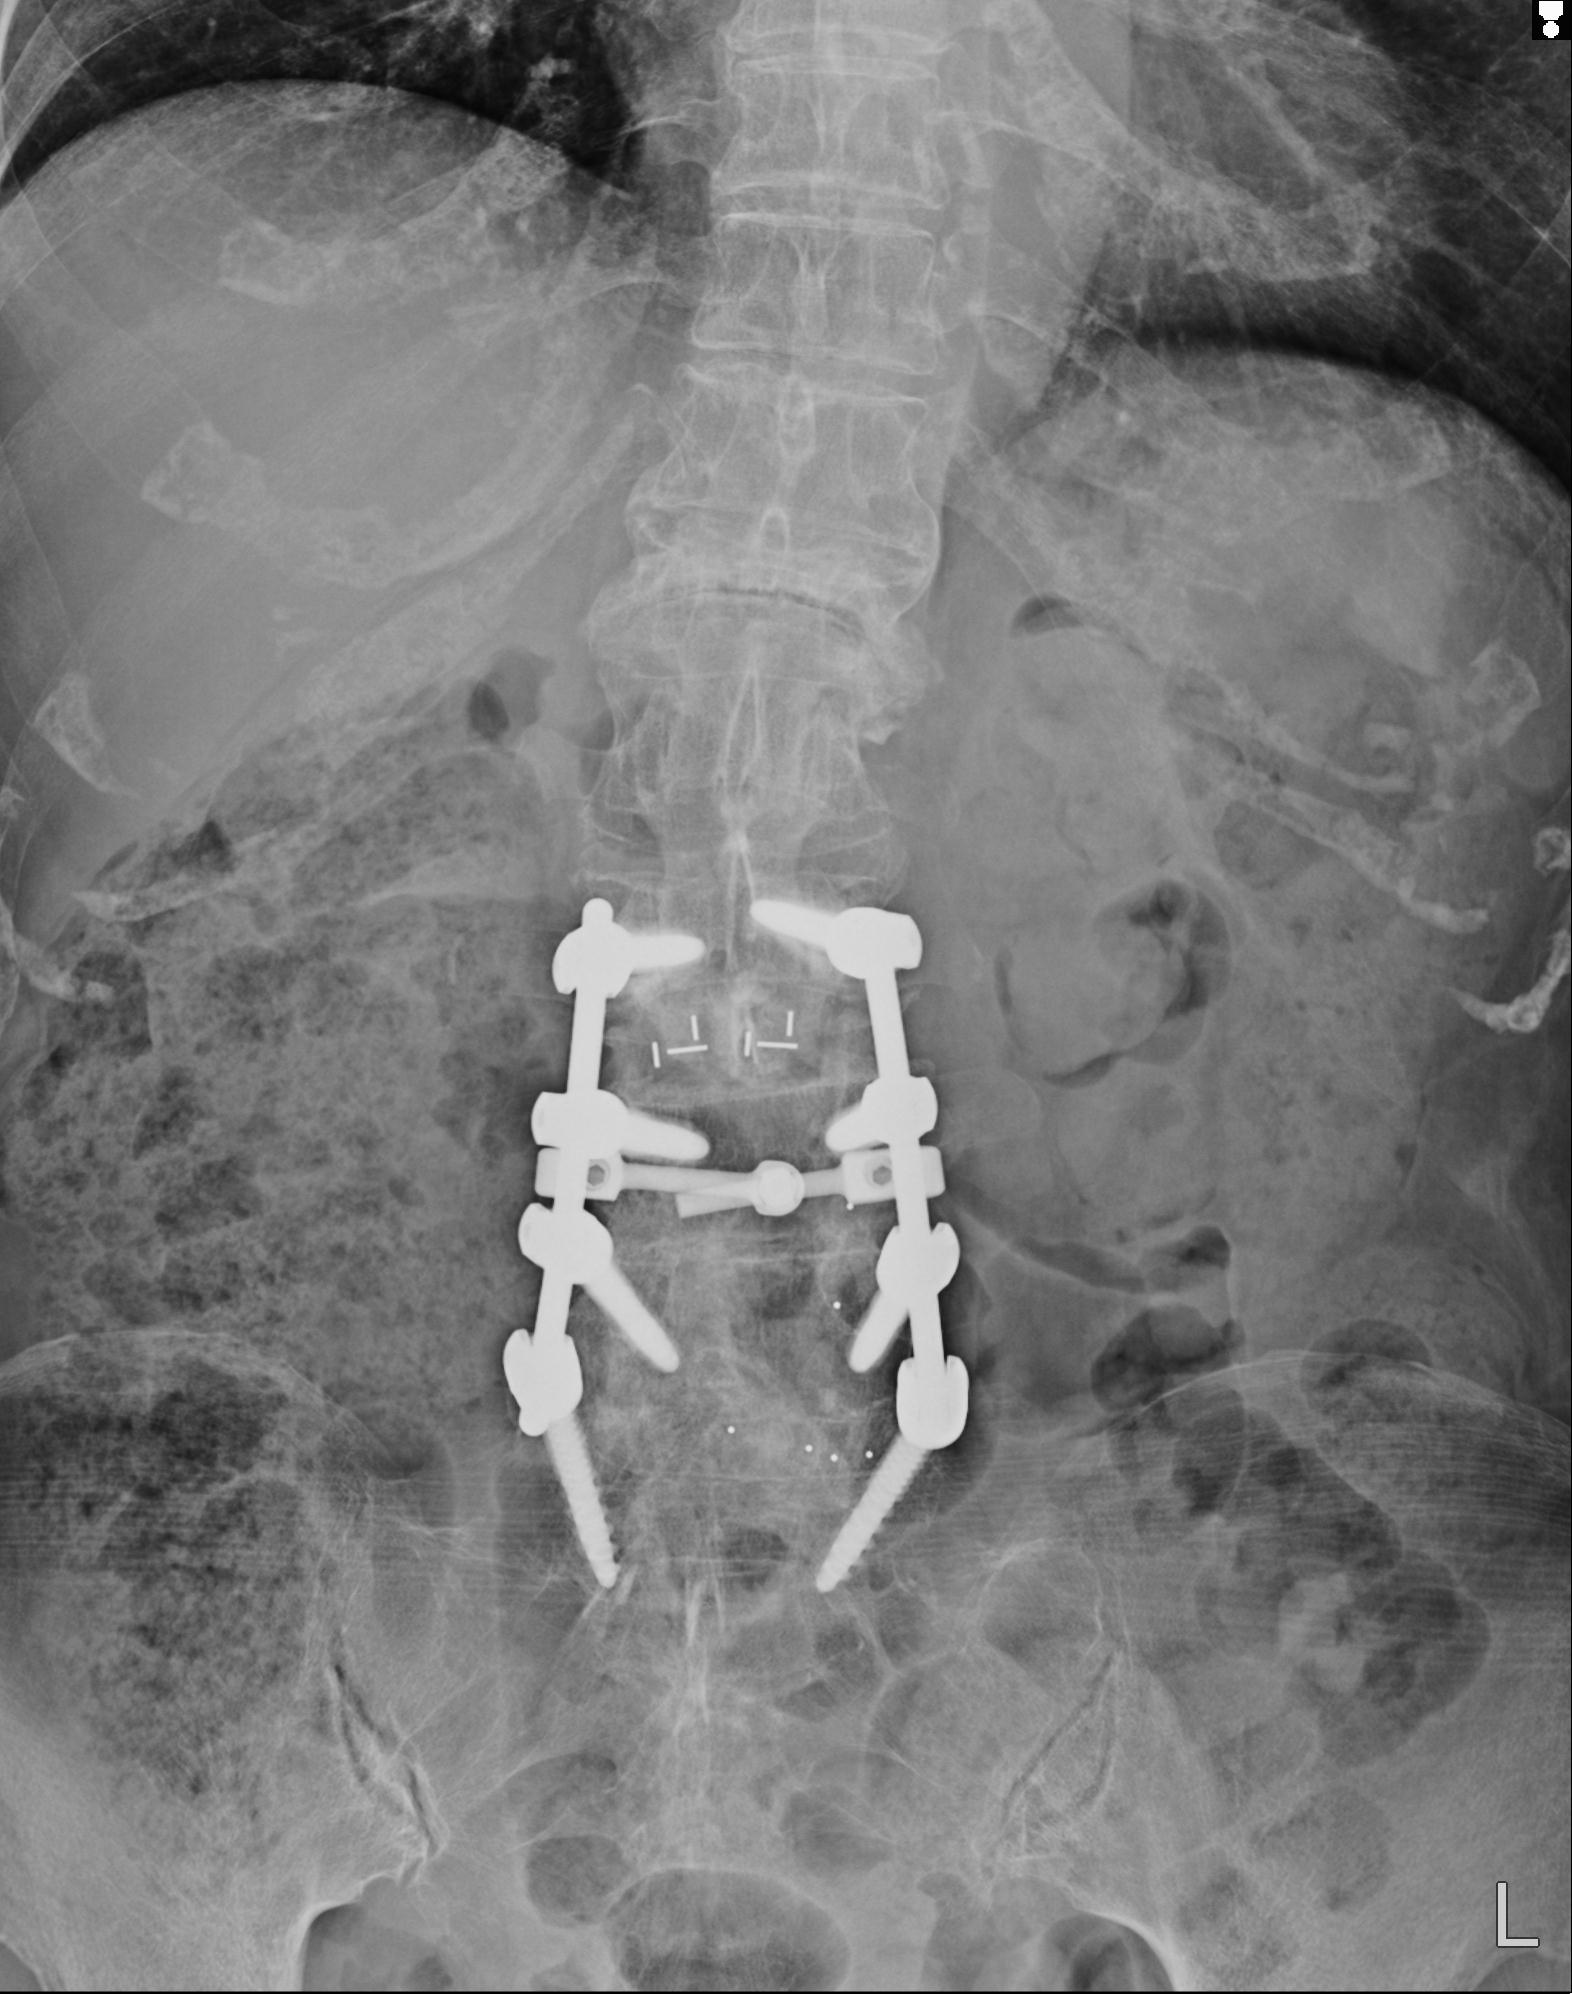

102916 2/1 と 3/22 腰椎 2R 74歳女性 LIFX